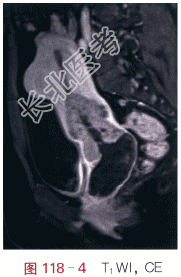

影像学资料如图118-1~图118-4所示。

读片分析:宫颈见内生型肿块,自宫颈外口向颈管内生长,侵犯宫颈深部组织,宫旁组织未受累,T₁WI呈等信号,T₂WI稍高信号,信号较均匀;增强后,瘤体强化较明显、欠均匀,但低于邻近正常的子宫。